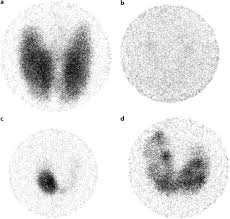

Graves' disease is an autoimmune disorder which directly impacts the tsh receptors of the thyroid. Hyperthyroidism is the state of the increased level of free thyroxin hormones which can be due to various causes including the graves disease. Graves' disease with hyperthyroidism is characterized by the presence of diffuse thyroid enlargement, suppression of pituitary tsh, elevations of thyroxine (t 4) and/or triiodothyronine (t 3), the presence of tsh receptor antibodies in the blood, an elevated radioactive iodine uptake by the thyroid gland and clinical symptoms such as weight. Patients with graves' disease often have enlargement of the thyroid gland and become hyperthyroid. This is the main difference between graves disease and hyperthyroidism. Graves' disease is the most common cause of hyperthyroidism, accounting for 60 to 80 percent of all cases.8 it is an autoimmune disease caused by an antibody, active against the thyroid. While it cannot be cured through diet, its symptoms can be reduced or alleviated in some people. In some cases, thyroid cancers may also cause an. Although a number of disorders may result in hyperthyroidism, graves' disease is a common cause. Graves' disease is one of three primary causes behind hyperthyroidism. Graves' disease is an immune system disorder that results in the overproduction of thyroid hormones (hyperthyroidism). Graves disease is a pathological condition which is defined as an autoimmune thyroid disorder with an unknown etiology. Antibodies usually help the body fight infection, but these antibodies stop the body from controlling the thyroid gland correctly (like a car without brakes).

Graves' disease with hyperthyroidism is characterized by the presence of diffuse thyroid enlargement, suppression of pituitary tsh, elevations of thyroxine (t 4) and/or triiodothyronine (t 3), the presence of tsh receptor antibodies in the blood, an elevated radioactive iodine uptake by the thyroid gland and clinical symptoms such as weight.